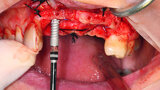

Fig. 14: Testing of the sterilised

surgical drilling guide proved drilling would be at the centre of the reconstructed bone ridge.